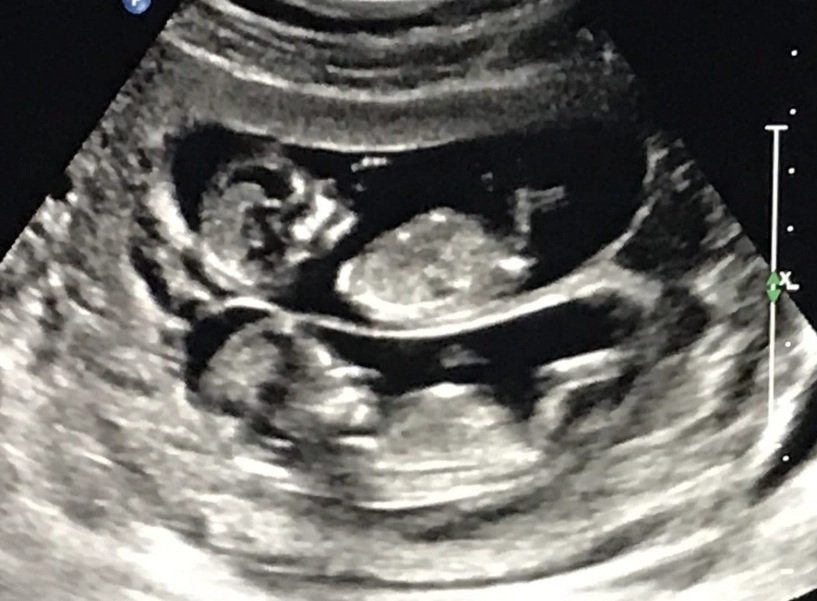

You might have had an earlier scan around 6-8 weeks, maybe to confirm the pregnancy or check the heartbeat. That one's important, sure, but it's often just a little blob and a flicker. The 12 weeks pregnant ultrasound is different. It's the first major, detailed check-up for your baby. Think of it as the end of the first trimester graduation exam.

They'll point things out as they go: "There's the head," "See the heartbeat flickering," "Those are the little arm buds moving." You'll likely see your baby bouncing, stretching, or even sucking its thumb. It's utterly mesmerizing.

This is the headline act. The sonographer will zoom in for a perfect side-profile view of the baby and measure the translucent (fluid-filled) space at the back of the neck in millimeters. The measurement increases naturally with the baby's size, so it's assessed against the crown-rump length.